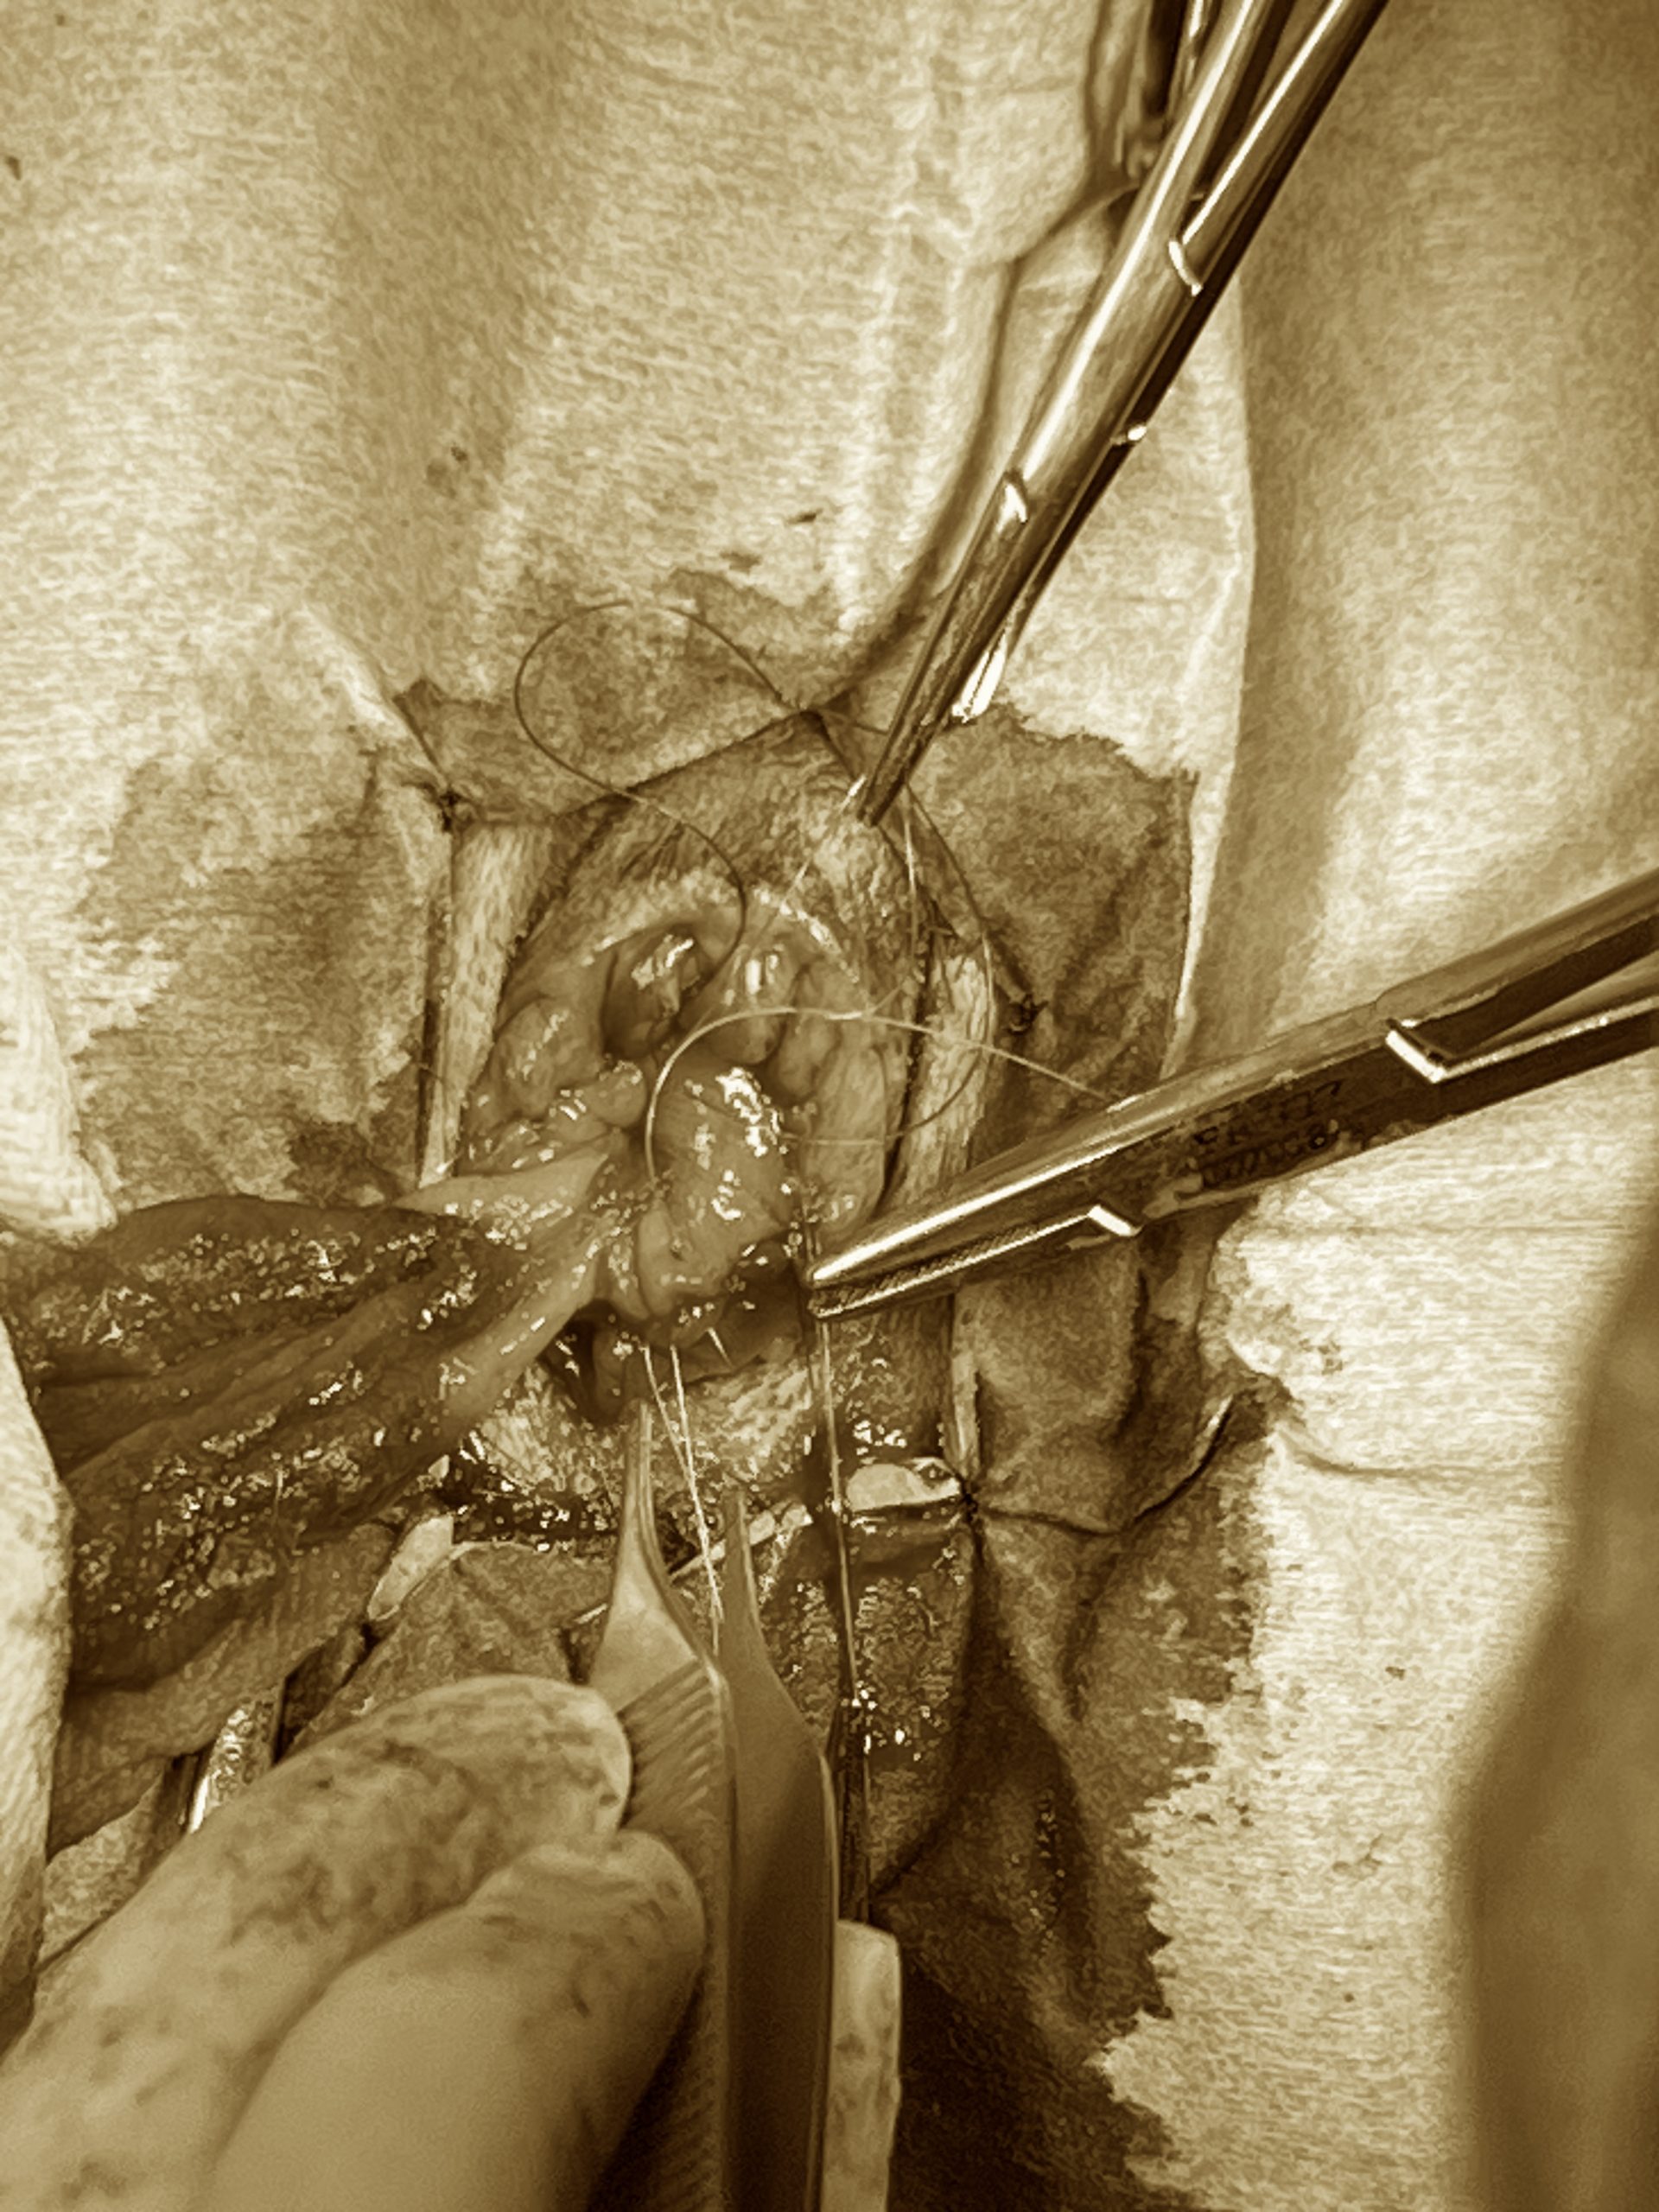

胆嚢摘出

胆嚢粘液嚢腫、胆嚢炎、胆管肝炎の感染巣として胆嚢が存在する場合、胆嚢摘出術を行います。 狩猟して生きていた頃、食べられない時間が長いが、獲物を捉えて食べられた時は一気に食べる、といった生活をしていた頃、胆嚢という袋に胆汁という消化酵素を貯留し、食べられるときに一気にその酵素を出し、できるだけ高率よく消化吸収を行える様にしていました。 ただ、飼育する様になり、毎日ご飯を食べられる様になった生活様式では、わざわざ胆汁を貯留する必要がなくなりました。そのため、毎日ご飯が食べられる環境にいるのであれば胆嚢は摘出しても目に見える様な影響はありません。 胆嚢摘出術は、炎症が顕著でなければ、胆嚢の最外層の腹膜を分離することで出血や肝臓組織の損傷を抑えて実施できます(写真1)。胆嚢管の部位でその膜をまた切離して胆嚢管は結紮離断します。 粘液嚢腫など総胆管に閉塞物がある状況の時はカテーテルを入れていき、開通性を確認します。確認できないときは十二指腸切開をして、大十二指腸乳頭から総胆管へアプローチします。フラッシュは特に逆行性にはしない様にしております、膵炎の発症に関わっているとされます。個人的には順行性にもなるべくしない様にしています。カテーテルが十二指腸へ入るのであれば、その必要性はあまりないと思われます。しかし、明らかに総胆管に閉塞し得るデブリスや胆石があるならばケースバイケースで実施しますが、この辺りはやるやらないの明確な線引きがありません。状況次第で判断します。 今後は、あまり癒着など強くない場合は腹腔鏡での胆嚢摘出がメインになってくると思います。炎症が強い場合や癒着が強い場合は、やはり開腹下での治療が必要です。 また、胆嚢摘出を実施するケースでは、ほとんどの場合、同時に肝生検を実施します。肝臓組織の変化を診て今後の治療に繋げていきます。